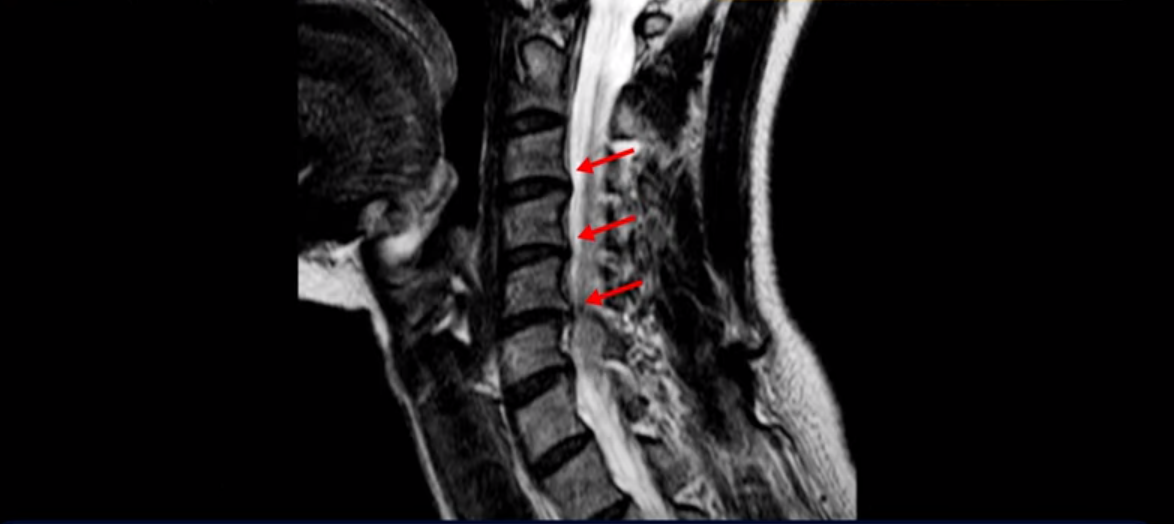

그런데 이분 목을 보시면 여러 마디의 뼈가 퇴행이 진행되어 있습니다. 뼈가 깍두기처럼 각지고 예뻐야 하는데 끝이 조금씩 변형되어 뾰족하게 자라고 있습니다.

이런 게 협착을 일으킵니다. 그래서 우선 오른쪽 신경구멍 즉 추간공을 살펴보면 맨 위의 한마디를 빼고는 다 좁아져 있습니다.

특히 5번 6번 구멍이 가장 좁습니다. 이걸 협착이라고 합니다.

사실 여러 신경 구멍이 다 좁아져 있기 때문에 정확히 어느 마디가 방사통을 일으키는지 정확히 알기 어렵습니다. 그래서 만일 수술을 한다면 정확히 어느 마디가 진짜 원인인지 파악하지 못한 채 한다면 수술이 크게 실패할 수도 있습니다. 또한 이분처럼 여러 마디가 안 좋아서 수술한 마디의 위나 아래가 상태가 좋지 않으면 유합술 후 그 위나 아래에서 또다시 문제가 생기는 인접 분절 질환이 수술 후에 발생할 수도 있습니다. 이런 정도는 알아두는 게 좋습니다.

목 치료가 쉽다고 하는 것은 이러한 근육치료가 허리에 비해 훨씬 더 쉬운 겁니다. 목 근육이 허리 근육에 비해 훨씬 구조도 단순하고 치료하기도 쉽습니다. 또 목은 머리만 받치고 있기 때문에 허리에 비해 부담을 적게 받습니다. 그래서 치료하기가 훨씬 더 쉽고 빠른 겁니다. 이분 목 X-RAY를 보면 일자목이면서 커브도 매우 좋지 않습니다. 이런 일자목, 거북목 상태에서는 목 주변 근육이 만성적으로 굳어있고 뭉쳐 있을 가능성이 매우 높고 그러니까 만성적인 목 통증이 있는 겁니다. 이런 뭉치고 굳어있는 근육이 목뼈를 심하게 잡아당기면 신경 자극 증상이나 신경 눌림 증상이 생기기 쉽습니다.